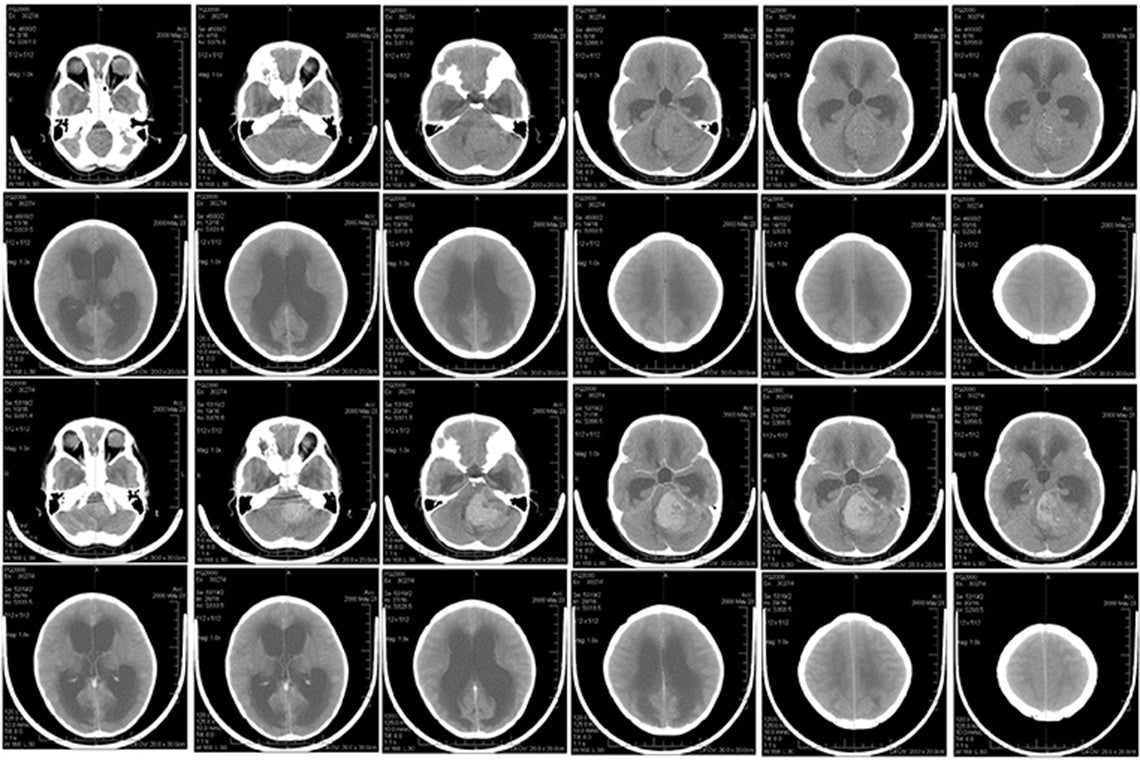

A team of researchers from the University of Toronto’s Donnelly Centre for Cellular & Biomolecular Research and McMaster University have made a potential breakthrough in medulloblastoma, a form of brain cancer that predominantly affects children and infants – a finding that could lead to new, targeted treatments that are less harmful to developing brains.

The researchers focused on group 3 medulloblastoma, caused by an overabundance of the MYC protein that spurs cell proliferation. These tumours are “a particularly sinister subtype” as they often spread prior to diagnosis and recur, says William Gwynne, a former post-doctoral researcher in the Singh lab and first author on the paper.